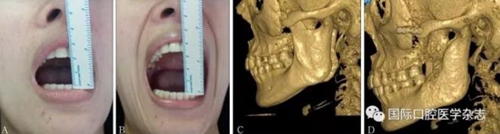

A:術前開口度;B:術后開口度;C:術前影像學檢查片;D:術后影像學檢查片。

圖 19 關節(jié)成形術前后對比